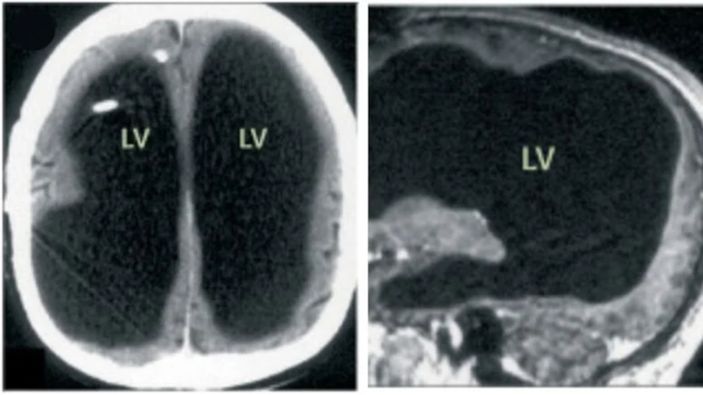

Beyin taraması sonrası adamın beyninin yarısının olmadığı, "Hidrosefali" adı verilen kafatasında ince bir beyin dokusu tabakası ve sıvı bulunduğu ortaya çıktı.

Doktorlar, hastalığının nedeninin beyninde biriken sıvı olduğunu ve bu durumun 30 yıl boyunca beyninin büyük kısmının tahrip olmasına yol açtığını düşünüyor.

Öte yandan hastalık bebekken teşhis edilmiş ve stent takılmıştı. Ancak 14 yaşındayken stent çıkarıldığında, beyninin büyük bir kısmı aşınmaya başladı.